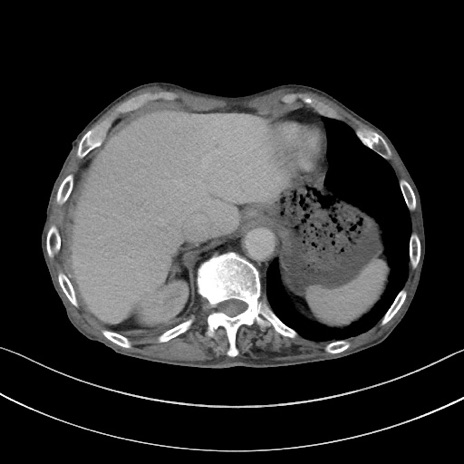

症例3(横断像)

【症例】 70歳代男性

【主訴】右鼠径部腫瘤、疼痛

【現病歴】本日朝より上記主訴あり、受診。

【既往歴】膀胱癌にて膀胱全摘、両側尿管皮膚瘻

【データ】WBC 5600、CRP 0.56